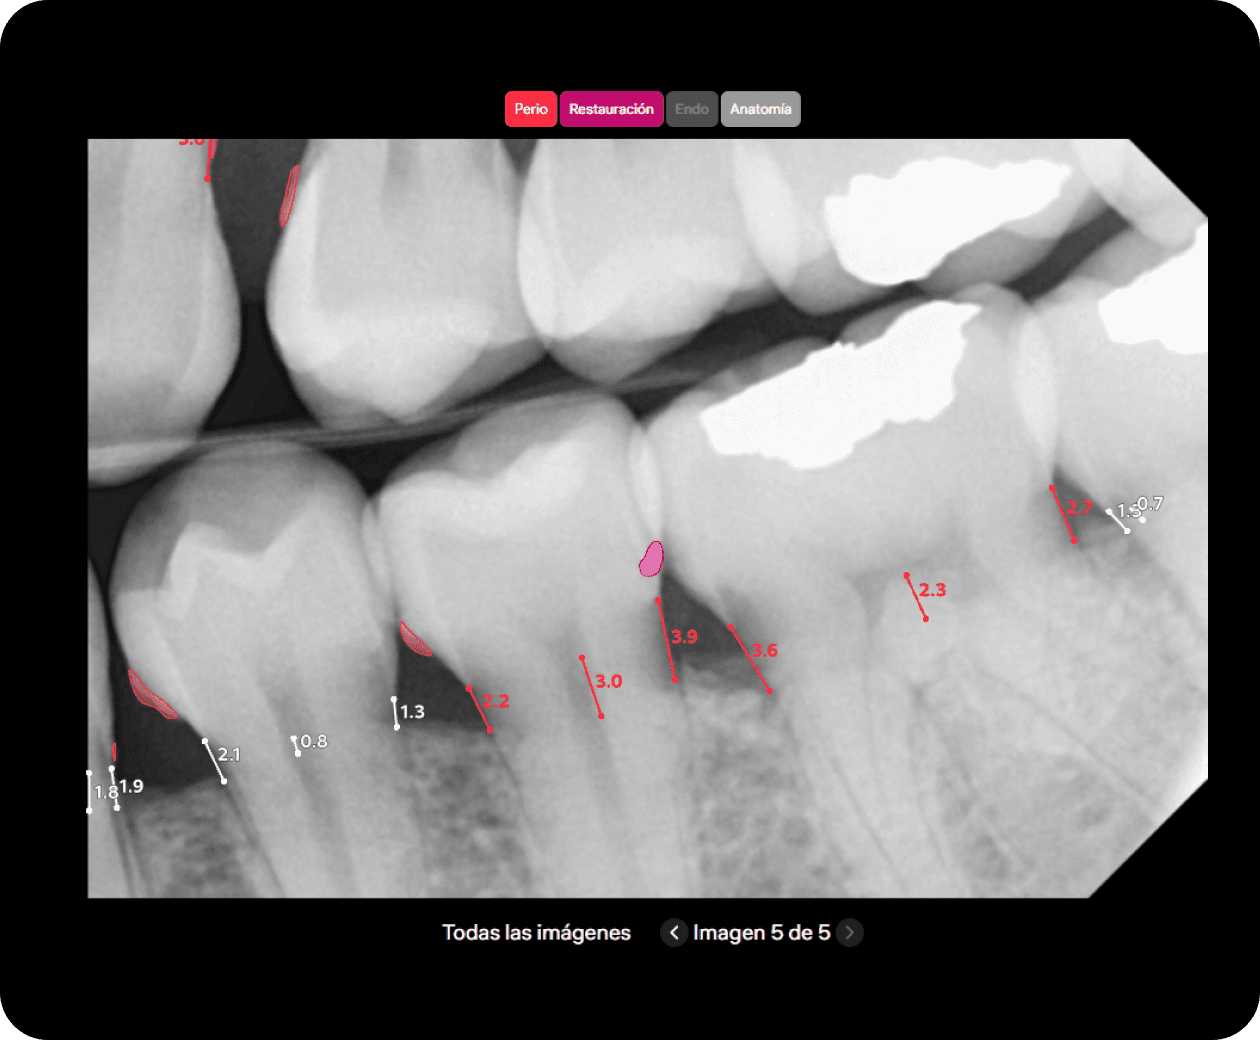

Diagnocat analiza imágenes radiológicas, simplifica la comunicación médico-paciente y motiva al paciente a iniciar el tratamiento.